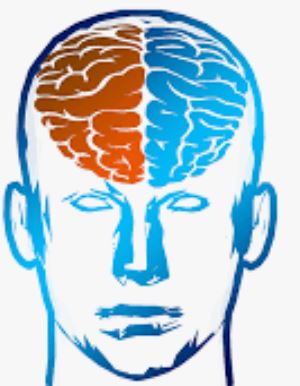

■ Le diagnostic médical sera fait dans la plupart des pays francophones sur la base de 2 à 3 entretiens avec un psychiatre ou un neurologue. Le TDAH peut être mis aussi en évidence par une IRM (images des deux cerveaux ci-dessous), même si cela n’a pas valeur de diagnostic.

► C’est un déterminisme génétique (donc héréditaire), qui entraine, du point de vue neurologique, une mauvaise régulation de deux neurotransmetteurs principalement (excès ou carence) , la Dopamine et la Noradrénaline, notamment au niveau du lobe frontal et spécialement sa partie derrière le front, le cortex préfrontal (schéma ci-contre). – La Dopamine sert à réguler les circuits de la récompense, du plaisir, de l’énergie, de l’attention, de la vigilance et de la motivation. – Leur présence irrégulière dans les connexions entre les neurones au niveau de l’axone (schéma ci-dessus) entraine une inconsistance de l’attention, du plaisir et de la motivation, notamment pour les tâches ou les relations de la vie de tous les jours. ► Le cortex frontal sert à programmer, planifier, inhiber des comportements impulsifs, mais aussi avoir une bonne flexibilité mentale. Il doit en effet être capable de s’interrompre si quelque chose de prioritaire survient en pleine action. — Pour être attentif, on a besoin d’une bonne transmission de la dopamine dans ce cortex frontal, ce qui n’est pas souvent le cas avec le TDAH. – Cela se traduit de manière différente selon que l’on est dans une phase hyperactive ou hypoactive : – Si je suis hypoactif, c’est-à-dire avec peu d’énergie, je pense à une chose à faire qui me fait penser à autre chose, puis d’autres pensées arrivent encore. – Un haut potentiel associé à une des 8 formes formes d’intelligences recensées (mathématique, verbale, musicale, corporelle, visuelle, interpersonnelle, intrapersonnelle), peut construire une arborescence d’idées créative. – Mais souvent au final je n’ai rien fait, car je suis resté dans ma tête, et, de plus, je n’ai souvent rien mémorisé, car ce sont des pensées furtives non propices à la mémoire de travail. – Si je suis hyperactif, je commence une tâche, je l’interromps pour commencer autre chose puis autre chose sans lien avec la tâche prioritaire initialement commencée (hyperactifs). – j’ai fait une multitude de tâches ou j’ai parlé abondement, la plupart du temps sans intérêt par rapport à mes priorités et aux attentes des autres personne. ► Du point de vue neurologique, les fonctions exécutives sont regroupées en 6 familles (avec l’acronyme : A.F.F.A.M.É.E) : – ACTIVATION : s’organiser, structurer, synthétiser, prioriser, décider, initier la tâche en gérant le temps – FOCUS : maintien de l’effort et de la vitesse d’exécution, ou basculement vers une tâche prioritaire – ACTION : autorégulation des actions, ralentir, s’activer ou s’adapter selon les situations/personnes – MÉMOIRE : capacité à conserver et rappeler l’information en mémoire durant une tâche/conversation – ÉMOTIONS : savoir moduler l’émotion pour ne pas s’emporter facilement, savoir gérer la frustration – EFFORT : ne pas perdre l’intérêt dans la tâche et faire face aux difficultés dans un temps donné  ► Chacune de ces 6 familles de fonctions exécutives peut poser un problème si on a un TDAH. On parle aussi de syndrome dysexécutif. ⇒ Chacun peut faire son propre bilan neuropsychologique chez un neurologue moyennant finance, mais on peut résumer ci-dessous les principaux problèmes que rencontre la majorité des enfants et adultes TDAH : – Problèmes d’attention focalisée (concentration) et divisée (suivre plusieurs informations en simultané) – Problèmes de gestion des informations stockées dans la mémoire à court terme (mémoire de travail) – Capacité d’inhibition : il s’agit d’une difficulté à empêcher ou à freiner des comportements et paroles inadaptées. – Problèmes dans la formulation d’objectifs, l’anticipation, l’élaboration de stratégie et la prise de décision – Problèmes dans la planification, l’organisation, la gestion des priorités et la gestion du temps. ► Cette liste de déficits est insupportable pour ceux qui ont misé sur un style de vie ou un type de métier qui n’autorise pas ces dysfonctionnements. – Ces déficits des fonctions cognitives et exécutives peuvent être un obstacle si on veut construire une vie trop conventionnelle nécessitant de la rigueur et de la régularité, avec beaucoup de frustration et le sentiment de ne pas s’accomplir. – D’où la nécessité de bien se connaitre pour faire des choix de style de vie, d’objectifs et de métiers compatibles avec cette particularité neurologique, ainsi que respecter ses besoins et valeurs. – Toute forme de forte et saine motivation peut permettre de générer la dopamine et noradrénaline nécessaires pour avancer durablement sur ses projets. – Une bonne hygiène de vie, de l’exercice physique, des pratiques psychocorporelles pour calmer le mental permettront d’atténuer cette inconsistance en neurotransmetteur (voir plus loin le manuel d’auto-coaching). |